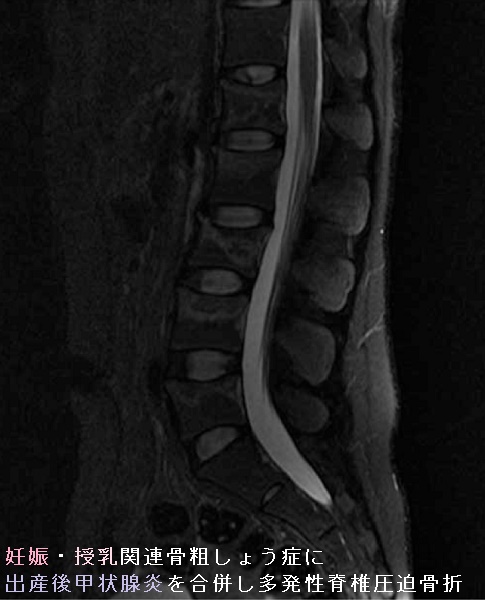

妊娠/授乳関連骨粗しょう症に出産後甲状腺炎を合併すると骨分解は加速され、多発性脊椎圧迫骨折に至る可能性があります。[Medicine (Baltimore). 2021 Oct 29;100(43):e27615.]

妊娠・授乳関連骨粗しょう症に出産後甲状腺炎を合併し多発性脊椎圧迫骨折 MRI T2強調画像

妊娠授乳関連骨粗しょう症に出産後甲状腺炎を合併した多発性脊椎圧迫骨折 MRI T2強調画像 [Medicine (Baltimore). 2021 Oct 29;100(43):e27615.より改変]